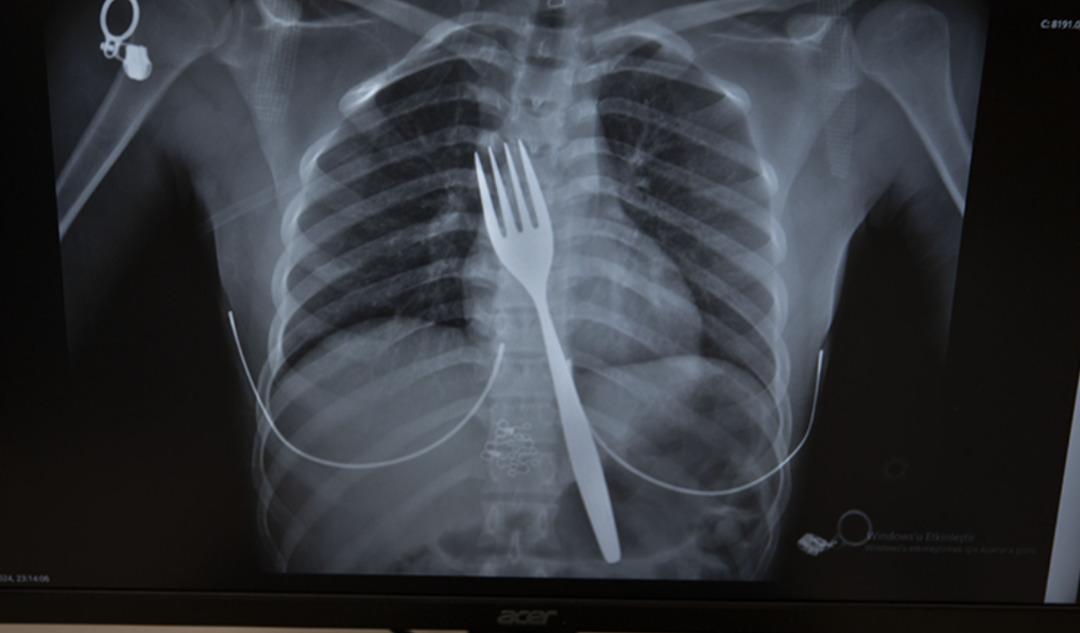

Söke’de ikamet eden yabancı uyruklu EE (18), çatal yutma şikayetiyle ambulansla Aydın Adnan Menderes Üniversitesi Hastanesi’ne (ADÜ) götürüldü. Burada röntgeni çekilen hastanın yemek borusunda 18 santimetrelik çatal olduğu belirlendi.

Uzmanlar endoskopi yaparak çatalı ağızdan çıkarmaya çalıştı. Ancak yemeğe ve nefes borusuna zarar verme ihtimali nedeniyle midenin kesilip çatalın çıkarılmasına karar verildi.

ADÜ Tıp Fakültesi Göğüs Cerrahisi Anabilim Dalı Öğretim Üyesi Dr. Salih Çokpınar ve Genel Cerrahi Anabilim Dalı Dr. Öğretim Üyesi Akay Edizsoy’un koordine ettiği operasyonda midede kesi yapılarak çatal çıkarıldı.

Edizsoy, vakayı ilk duyduğunda şaşırdığını belirterek, şöyle konuştu: “Büyük bir çatalın tamamen yutulması sonucu oluşan bu vakayı ilk duyduğumda doğru olmadığını düşünmüştüm. Hasta 18 yaşında ve 18 yaşındaydı. Yabancı uyruklu. Türkçesi biraz zayıf olduğu için bir yanlış anlaşılma olabileceğini düşündük ama hastayı çektiğimizde aslında çatal yutuyordu.” “Yemek borusunda olduğunu gördük.” dedi.

“Bu yüzden çok endişelendik. Ancak endoskopide ciddi bir lezyonun olmadığını gördük. Oldukça büyük olduğundan ve endoskopik aletlere uygun olmadığından endoskopi ile çıkarılamadı. Büyük bir masa çatalı olduğu için kendine ait. ağırlıktır. Bir çivi gibidir, bir iğne gibidir. “Tutulamaz ve çıkarılamaz. Bu nedenle karından kesi yaparak mideye ulaşıp midenin içinden çıkarma stratejisi izledik. Bu ameliyatla bu çatalı oradan çıkarmayı başardık.”